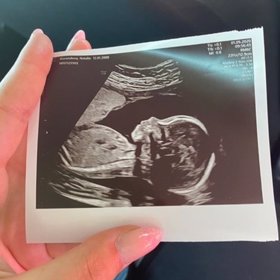

Dnes oznámila Natálie Kočendová tragickou zprávu na svých sociálních sítích. V šestém měsíci těhotenství přišla o svého syna, kterého čekala s Lukášem Vlačuhou neboli Laky Royalem. Modelka také sdílela svou první a poslední fotografii s miminkem, které se mělo narodit za 3 měsíce. K partnerce se později přidal i její přítel, který zveřejnil snímek z ultrazvuku.

Natálie pro svého zesnulého syna napsala dojemný vzkaz do nebe. „Navždy tady budeš s námi. Navždy budeš můj milovaný syn. Má fazolka. Takovou lásku a štěstí, jaké jsem zažívala šest měsíců s tebou, jsem nikdy nezažila. Nyní to vystřídala neskutečná bolest. Ztratila jsem kousek sebe,“ napsala Kočendová pod fotografií z nemocnice, kde drží chlapečka v rukou. „Dala bych vše za to, abych opět cítila tvé kopance a po porodu si tě mohla vzít zdravého domů,“ dodala v dojemném vzkazu. „Jsi ten nejkrásnější kluk. Jednou se tam nahoře potkáme. Miluji tě, moje malá lásko,“ ukončila truchlící Kočendová.